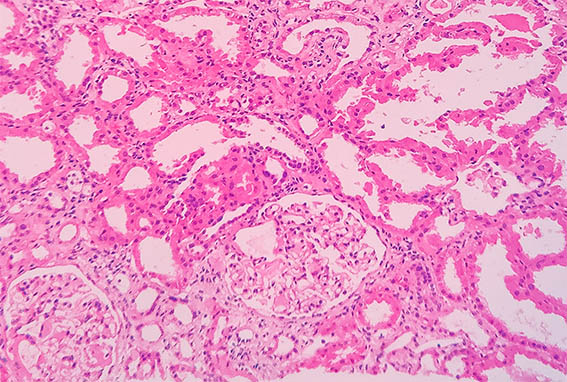

Un paciente de 53 años con diagnóstico de infección por VIH 2 años antes, en tratamiento anti-retroviral, es evaluado por 2 semanas de edemas, sin otros síntomas. En las pruebas de laboratorio el hemoleucograma es normal. Conteo de CD4: 510 /mm2; carga viral: menos de 500 copias /mL. Se documenta síndrome nefrótico, con proteinuria de 7,5 g/24h, hipoalbuminemia y dislipidemia. Creatinina sérica: 1,0 mg/dl, BUN: 14,0 mg/dL. Estudios para virus de hepatitis: negativos. ANAs y anti-DNA negativos; complemento sérico normal; VDRL no reactivo. Electroforesis de proteínas en suero: normal.

Se hace biopsia renal, observe las imágenes.

Figura 1. H&E, X200.